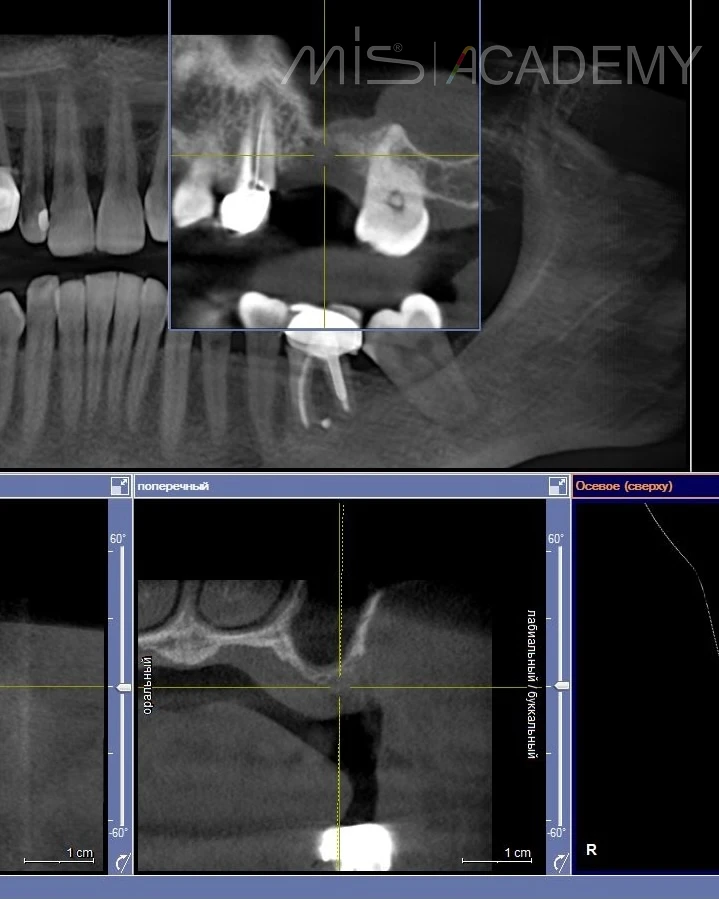

— На ОСЛ решили добавить колопол и PRF без костного материала.

— Через 3 месяца мы увидели рост кости 400HU , поэтому провели второй этап.